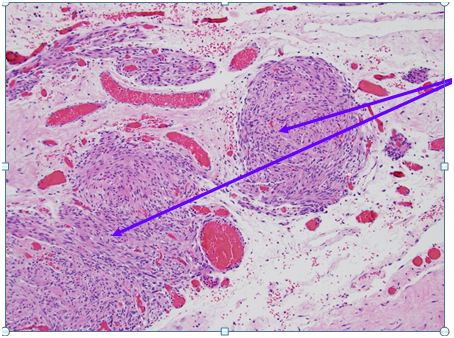

Figure 2 Higher Magnification of Box 1A from Figure 1: Smooth muscle arranged like leiomyomas / Nodules of smooth muscle bundles proliferation which are bland looking and lack mitoses = Leiomyomatosis (Purple Circles) Hematoxylin and Eosin Stain (H&E stain or HE stain). 1A: Sections show a low grade spindle cell proliferation, fascicular in appearance, forming small and large nodules. The spindle cells show no cytological atypia, and no mitoses are identified. The nodules are situated in a fibrous and vascular background with interspersed collections of decidualized cells. The spindle cells are positive for SMA, and are negative for Melan-A and HMB-45. The findings, combined with the clinical presentation, are compatible with disseminated peritoneal leiomyomatosis. A leiomyoma arising from the serosal aspect of the uterus is also a consideration, though considered less likely.